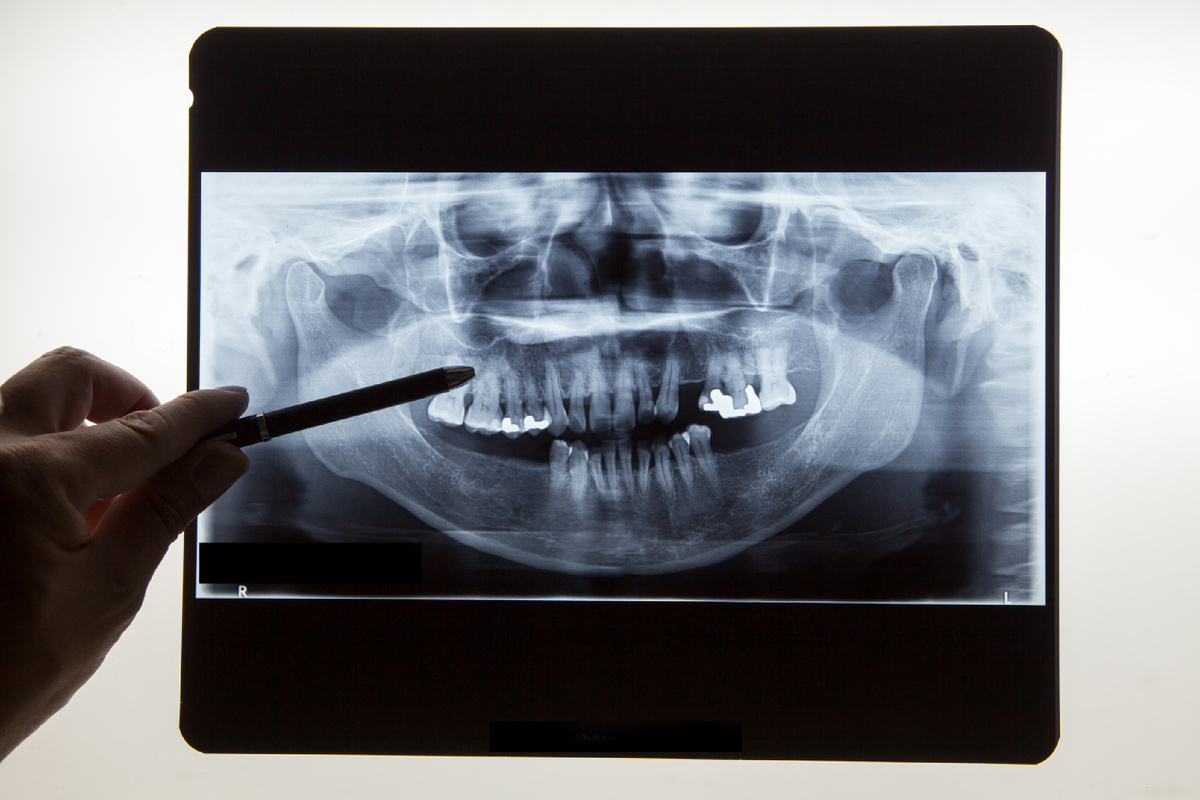

Как отсутствие жевательных зубов провоцирует гипертонус лицевых мышц и бруксизм. Отсутствие жевательных зубов — серьезная проблема, которая может привести к ряду функциональных и эстетических нарушений. Одним из таких последствий является развитие гипертонуса лицевых мышц и бруксизма. Жевательные зубы играют ключевую роль в процессе пережевывания пищи, равномерно распределяя нагрузку на челюсти. Их отсутствие нарушает этот баланс, заставляя другие зубы и мышцы компенсировать недостаток. Это приводит к перенапряжению лицевых мышц, что может вызвать их гипертонус. Когда жевательные зубы отсутствуют, нагрузка на челюсть распределяется неравномерно. Мышцы вынуждены работать интенсивнее, чтобы обеспечить нормальный процесс пережевывания. Постоянное напряжение приводит к их утомлению и развитию гипертонуса — состояния, при котором мышцы находятся в постоянном напряжении даже в состоянии покоя. Гипертонус лицевых мышц может стать триггером для развития бруксизма — непроизвольного скрежетания

Отсутствие жевательных зубов — серьезная проблема, которая может привести к ряду функциональных и эстетических нарушений. Одним из таких последствий является развитие гипертонуса лицевых мышц и бруксизма.

Жевательные зубы играют ключевую роль в процессе пережевывания пищи, равномерно распределяя нагрузку на челюсти. Их отсутствие нарушает этот баланс, заставляя другие зубы и мышцы компенсировать недостаток. Это приводит к перенапряжению лицевых мышц, что может вызвать их гипертонус.

Когда жевательные зубы отсутствуют, нагрузка на челюсть распределяется неравномерно. Мышцы вынуждены работать интенсивнее, чтобы обеспечить нормальный процесс пережевывания. Постоянное напряжение приводит к их утомлению и развитию гипертонуса — состояния, при котором мышцы находятся в постоянном напряжении даже в состоянии покоя.

Гипертонус лицевых мышц может стать триггером для развития бруксизма — непроизвольного скрежетания зубами. Постоянное напряжение и дискомфорт провоцируют организм искать способы разрядки, одним из которых является скрежетание зубами. Бруксизм, в свою очередь, усугубляет состояние мышц, создавая замкнутый круг.

Для предотвращения гипертонуса и бруксизма важно своевременно восстанавливать утраченные жевательные зубы с помощью протезирования или имплантации. Это поможет восстановить правильное распределение нагрузки и снизить риск перенапряжения мышц. Кроме того, регулярные консультации у стоматолога и использование специальных кап могут помочь в лечении бруксизма и снижении мышечного напряжения.

Таким образом, отсутствие жевательных зубов может значительно повлиять на здоровье полости рта и общее самочувствие, поэтому важно своевременно принимать меры для восстановления зубного ряда.